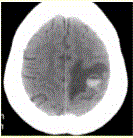

问题 患者女,55岁,右侧肢体无力3d。头颅CT显示如下图。 可能的诊断为(提示进一步询问病史,患者无血液系统病史,并行胸部CT检查,发现肺部肿块(下图)。)

选项 A.急性脑血肿 B.肺癌脑转移瘤伴出血 C.胶质瘤伴出血 D.少枝胶质细胞瘤伴出血 E.血液系统病变伴脑出血 F.脑脓肿 G.血管畸形伴出血

答案 B